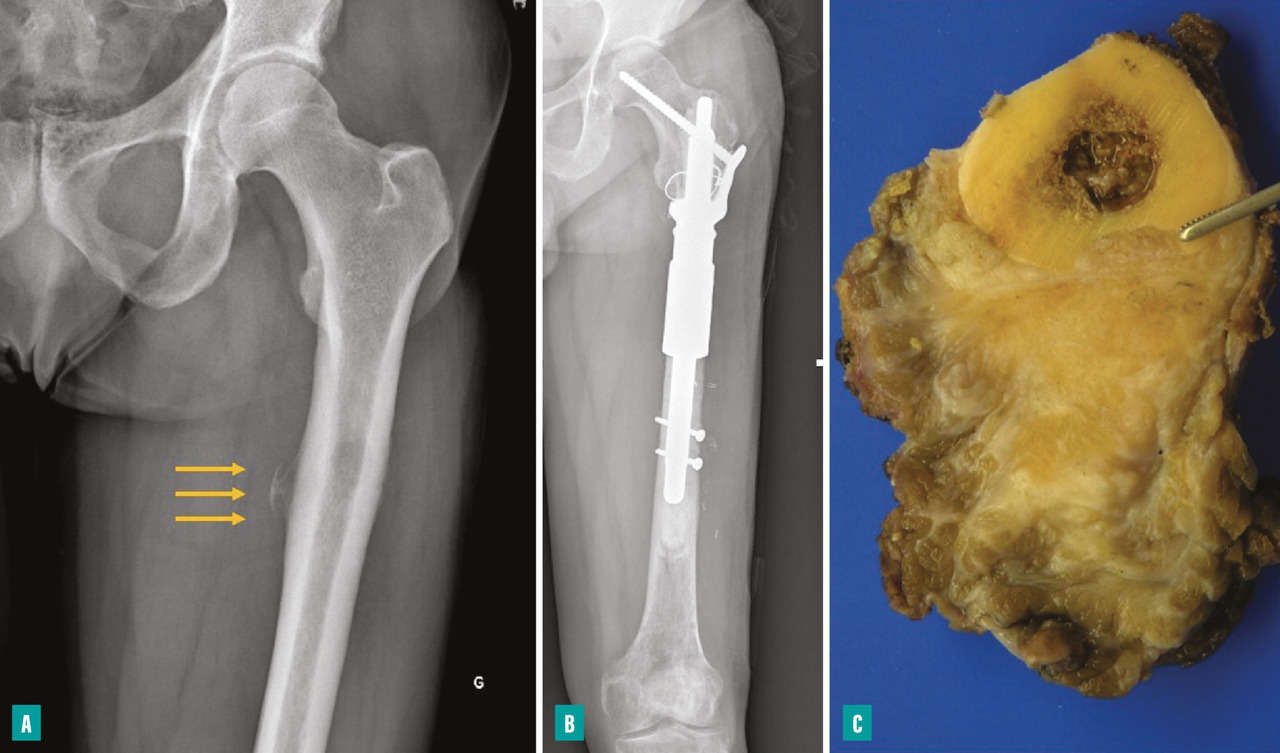

La survenue d’une fracture pathologique rend plus difficile l’obtention de marges saines du fait de la dissémination de l’hématome dans les tissus mous. Elle ne semble pas augmenter le risque de récidive locale – à la condition d’obtenir des marges saines – et ne constitue donc pas une indication d’amputation (fig. 3). Lorsqu’elle survient en cours de traitement, elle fait craindre une mauvaise réponse à la chimiothérapie, qui pourrait expliquer le moins bon pronostic de ces patients.3,4